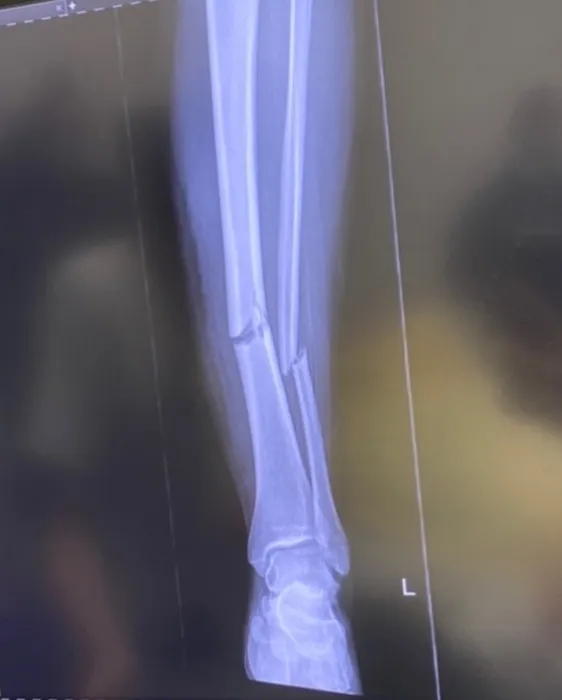

Teo Meluță a postat imaginile cu fractura care a dus-o pe masa de operație: „Mă așteaptă un drum lung și greu!” | FOTO & VIDEO